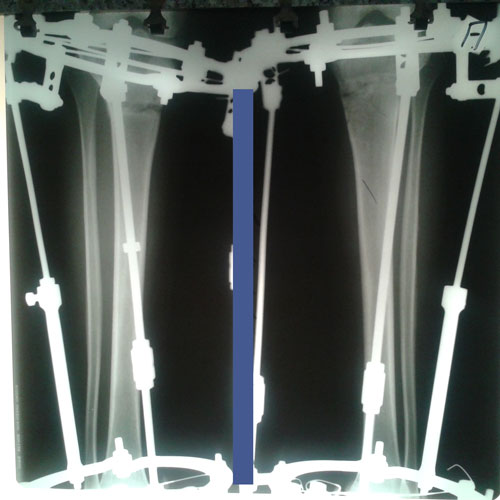

в процессе исправления деформации.

Рентген в 49 дней с момента операции.